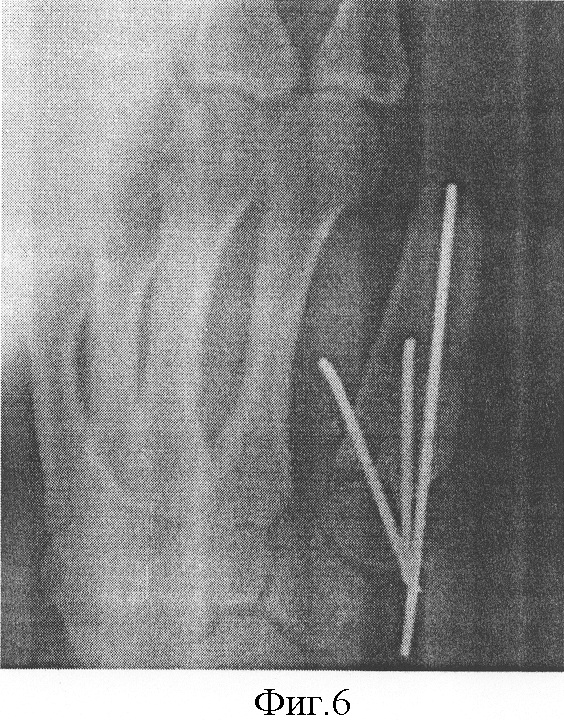

Под внутривенным обезболиванием поперечным тыльно-боковым разрезом в области культи 1 пястной кости выделили торец (конец) ее и в толще мягких тканей тупо сформировали туннель в дистальном направлении от культи до уровня второго пястно-фалангового сустава. На конце трансплантата сформировали углубление (канал). Костный трансплантат провели в туннель в сторону второго пястно-фалангового сустава, после чего заостренный конец культи пястной кости внедрили в углубление трансплантата продвижением его в центральном направлении, и фиксировали к культе пястной кости спицами. Швы на кожную рану, гипсовая лонгета. Контрольная рентгенография (Фиг.5, 6). Рана зажила первичным натяжением.